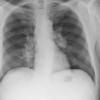

Lymphoma PA (DLBC)

Date: 04/25/2009

Views: 3515